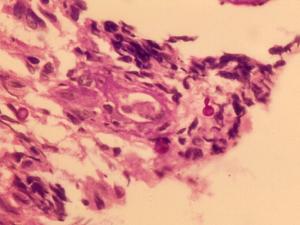

Photos show Sporothrix schenckii PAS stained tissue section showing budding yeast-like cells, culture at 25C and budding yeast cells in BHI at 37C, and conidiophores and conidia at 25C.

Colonies at 25C, are slow growing, moist and glabrous, with a wrinkled and folded surface. Some strains may produce short aerial hyphae and pigmentation may vary from white to cream to black. Conidiophores arise at right angles from thin septate hyphae and are usually solitary, erect and tapered toward the apex. Conidia are formed in clusters on tiny denticles by sympodial proliferation at the apex of the conidiophore, their arrangement often suggestive of a flower. As the culture ages, conidia are subsequently formed singly along the sides of both conidiophores and undifferentiated hyphae. Conidia are ovoid or elongated, 3-6 x 2-3 µm, hyaline, one-celled and smooth-walled. In some isolates, solitary, darkly-pigmented, thick-walled, one-celled, obovate to angular conidia may be observed along the hyphae. On brain heart infusion (BHI) agar containing blood at 37C, colonies are glabrous, white to greyish-yellow and yeast-like consisting of spherical or oval budding yeast cells.